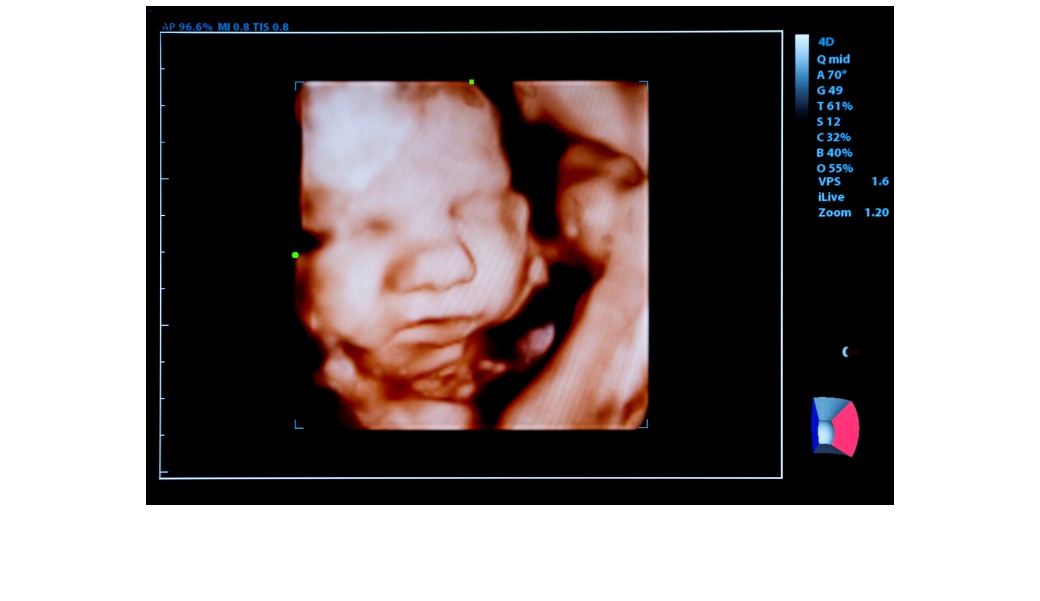

Айла, която живее в Канада с родителите си Захид и Собия, се подлага на експерименталното лечение през пандемичната 2021 година, докато е още в корема на мама. Лекарите бързат, защото има щети, които болестта нананася на плода и тези увреждания не могат да бъдат обърнати, без значение колко добро е лечението след раждането на бебето. Според лекарите може никога да не се постигне оптимален резултат. Семейството има две незасегнати деца на възраст 13 и 5 години. Но всяка бременност буквално е хвърляне на генетични зарове. След като пренаталните тестове показват, че поредното дете има болест на Помпе, майката на Айла е получила шест инфузии между 24-ата и 37-ата седмица от бременността. Ензимът се доставя във вената на пъпната връв на плода с помощта на игли, насочвани от ултразвук. Всяка доза се влива две седмици след предишната, за да се осигури нормално развитие на мускулите на плода, включително сърдечните.